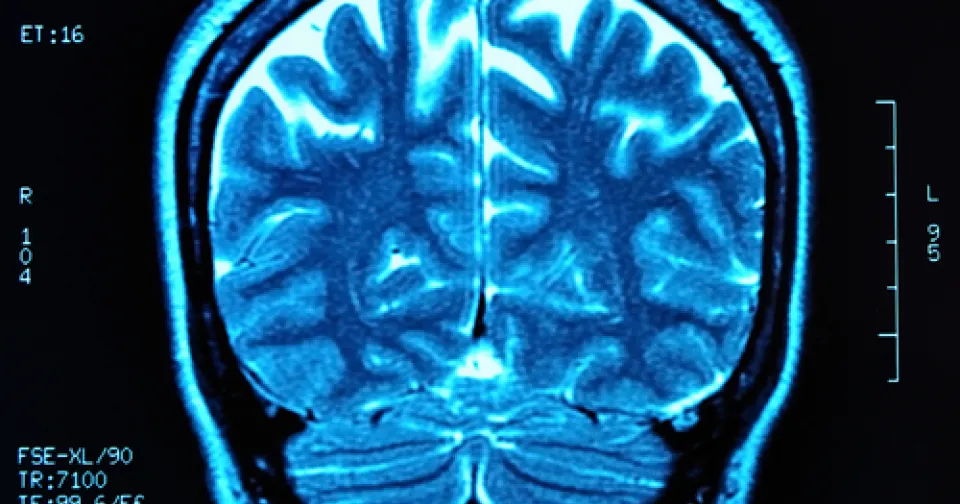

Take becoming a Neurodiagnostic Technologist (NDT). In short, technologists employ specialized equipment to determine how effectively a patient's nervous system is functioning.

The test results they gather enable physicians to diagnose and treat conditions such as degenerative brain diseases, headaches, dizziness, seizure disorders, strokes, mental disorders, and sleep disorders.